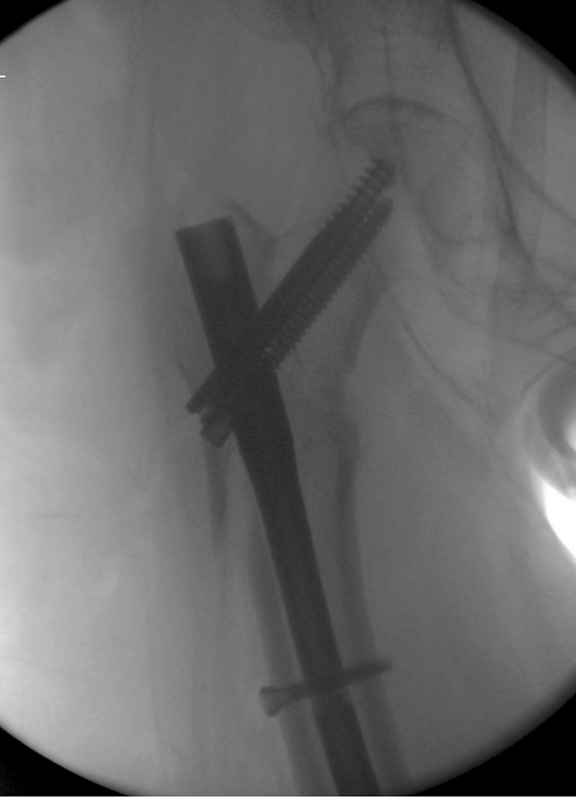

Здесь 83 года, травма в результате падения